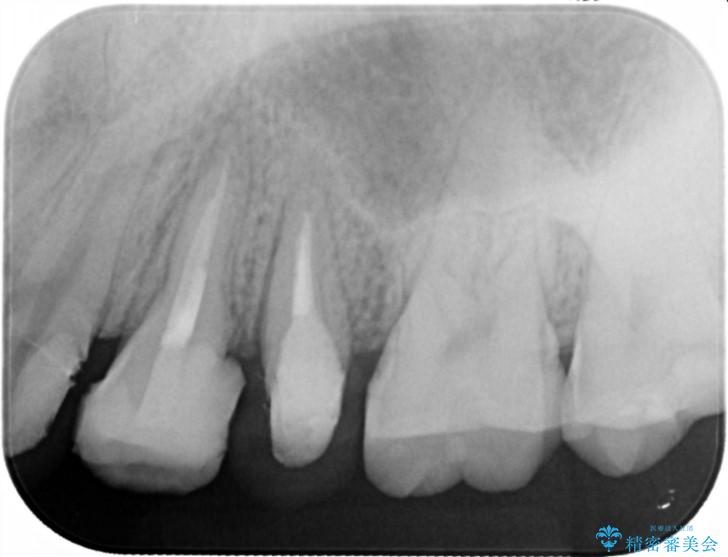

- 歯ぐきの腫れや、歯の内部が黒く見えることからの虫歯の治療を求めて来院されました。

虫歯が大きかったことから、神経の温存はできたものの歯ぐきよりも深い虫歯の問題を解決するため部分矯正治療を併用したセラミック治療を行うこととしました。

当初、歯ぐきよりも深い虫歯のぞんざいや、歯のポジションに問題がありましたがマルチブラケットを用いた部分矯正を行うことで適切な位置へと歯を移動させ、歯周環境を整えたセラミック治療を行うことができました。